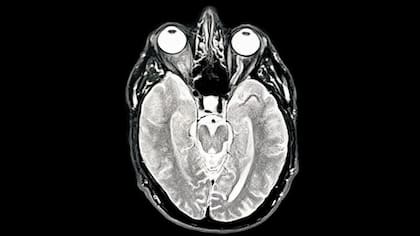

Tras comparar los cerebros de más de 3800 personas de entre 0 y 90 años a través de resonancias magnéticas que mapean las conexiones neuronales, los científicos encontraron esos cuatro puntos de inflexión que marcan el principio y el fin de “las edades del cerebro”. El hallazgo no es menor, sobre todo, si se tiene en cuenta que la forma en la que el cerebro está conectado está relacionada con trastornos neurológicos, mentales y del neurodesarrollo. “Al comprender los puntos de inflexión claves, podremos entender mejor a qué es más vulnerable el cerebro a diferentes edades. Cuanto más aprendamos sobre los cambios esperados en las conexiones cerebrales a lo largo de la vida, mejor podremos distinguir qué se considera un cambio saludable y típico de los signos de algo relacionado con una enfermedad o un trastorno”, explica Alexa Mousley, autora del estudio.